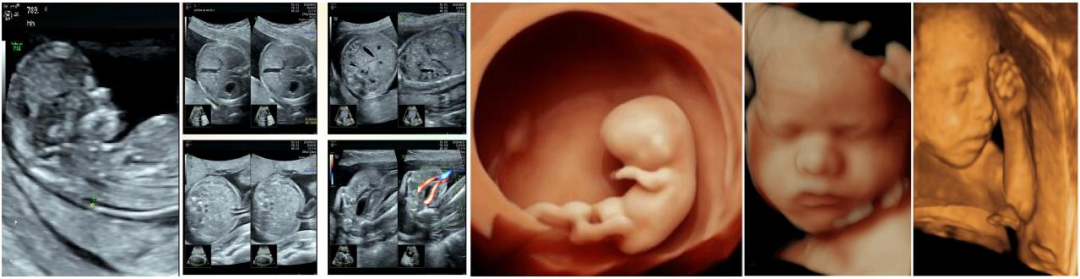

图为超声科部分产前超声筛查及三维、四维检查图

1. 产前胎儿超声筛查:科室2018年获取产前超声筛查机构资质,为地区较早开展产前超声筛查的单位之一。2.肾病血液透析前臂内瘘血管超声检查。3.超声声学造影、妇科盆底及产科三维、四维检查技术。4.新生儿颅脑、先心病筛查及肌骨超声检查。5.各脏器超声引导下穿刺活检术、胸腹水穿刺置管引流术、囊肿硬化治疗术等多种超声介入性技术。